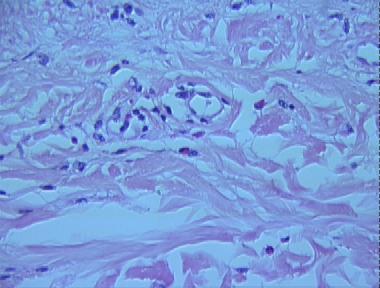

chronic urticaria

Histologic Features